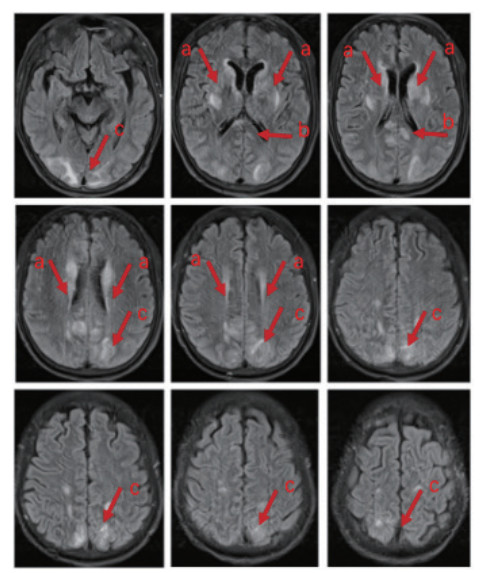

全程镇痛镇静,并行神经营养治疗(醒脑静针、甲钴胺针、四己糖神经节苷脂针、安宫牛黄丸)。第5天可呼唤睁眼,无遵嘱动作及四肢活动。第8天自主睁眼,仍无遵嘱表现,刺痛下肢屈曲,成功脱机拔管。第10天头颅MRI示“两侧基底节区、侧脑室旁、顶枕叶及胼胝体压部异常信号影,脑白质疏松,FazekasⅡ级”(图 2)。第13天自主睁眼,仍无遵嘱表现,发单音,刺痛定位,偶有自主活动,后行高压氧治疗。

注: 箭头a所指区域显示基底节区及侧脑室旁存在异常高信号影, 箭头b所指区域显示胼胝体存在异常高信号影, 箭头c所指区域显示枕叶顶叶存在异常高信号影 图 2 患者的头颅核磁共振影像

患者入院后持续昏迷,多次头颅CT检查未见异常。入院第10天,MRI显示双侧基底节、顶枕区及胼胝体压部异常信号,并伴脑白质病变。经治疗,患者意识逐步恢复,出院时GCS评分为E4、T2、M5,但仍存在明显意识内容障碍。研究表明,单氰胺中毒患者中73% 发生中至重度意识障碍(GCS < 13),其中80% 头颅CT正常,仅20% 出现不同程度脑水肿。严重脑水肿(≥ 4级)MRI影像常见双侧额叶、枕叶、脑室周围及深部白质信号异常,与本例MRI结果相符[11]。单氰胺中毒导致脑病的确切机制仍不明确,研究提示其可能与细胞缺氧应激反应相关。缺氧诱导因子-1α(HIF-1α)水平与GCS评分呈显著负相关,表明HIF-1α可能在单氰胺相关脑病的发生中起关键作用[11]